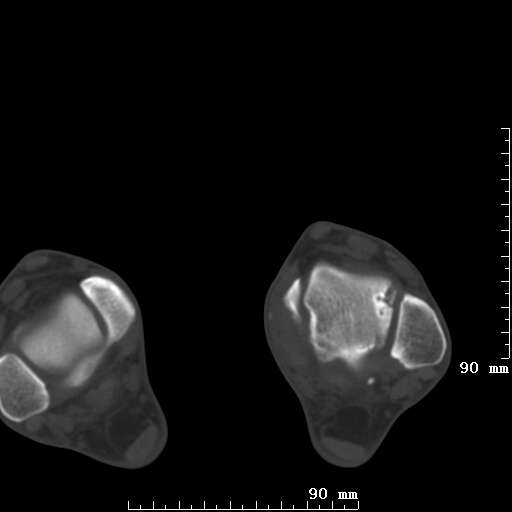

标题: CT19820:外伤一天,如何定性.男27Y [打印本页]

标题: CT19820:外伤一天,如何定性.男27Y

排除下创伤性关节炎吧,距骨有些囊变和硬化,周围韧带软组织有些机化、钙化。不是很像距骨无菌性坏死,感觉在关节面上的多,而不是距骨里面。

未见骨折及脱位像。距骨像是剥脱性软骨炎

支持!(踝关节距骨表面囊变和硬化 缺损)

距骨剥脱性软骨炎可能;踝关节创伤性关节炎?

未见明确新鲜骨折改变,距骨剥脱性软骨炎或踝关节创伤性关节炎可能。

关节周围多发高密度影,要结合病史